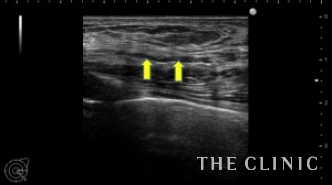

左はベイザーで脂肪を崩してから吸引しました。こちらもほとんど壊死脂肪はなくなりました。